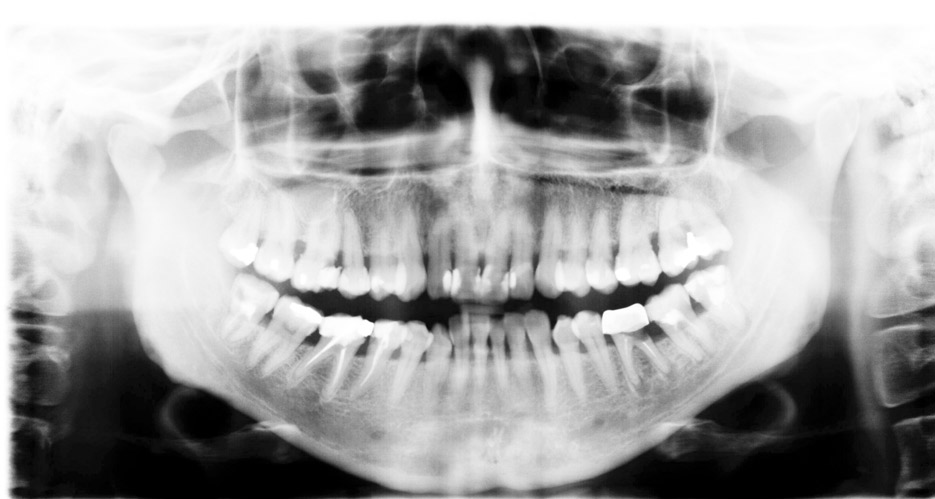

Radiografía panorámica u ortopantomografía

Es la más usual. Este tipo de radiografía da una imagen completa de toda la boca, por lo que es muy útil para tener una visión general. Es la que suele hacerse cuando el paciente viene a nuestra clínica dental en Valencia por primera vez, y también cuando viene anualmente a los sucesivos controles y mantenimientos. Se realiza con una máquina especial que rota alrededor de la cabeza. Se utiliza para planificar cualquier tipo de tratamiento: ortodoncia, implantes dentales, planear cirugías de extracciones de muelas del juicio, entre otros casos.